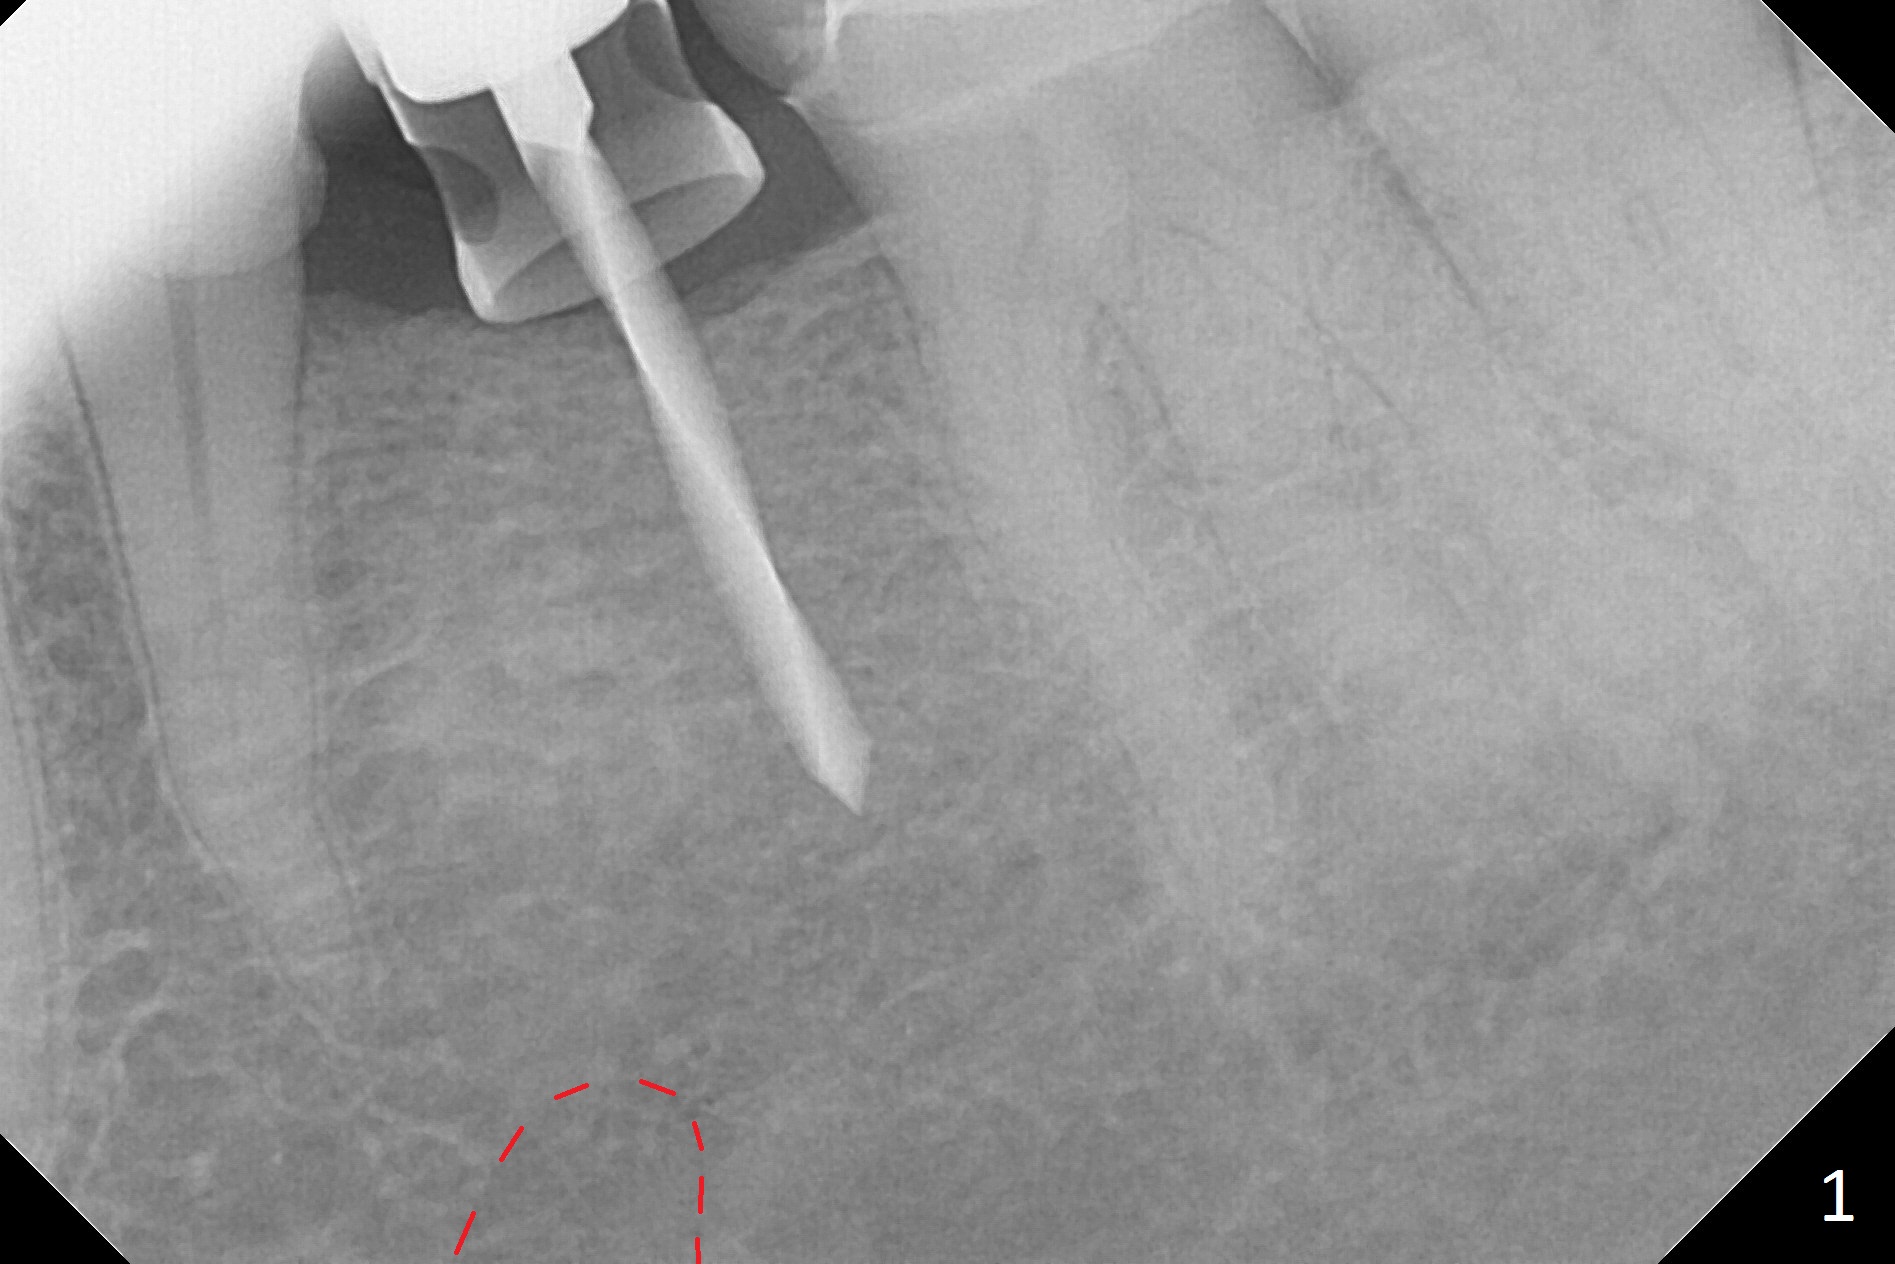

Initial osteotomy with 1.6 mm drill for 11 mm seems to be distal (Fig.1).  The trajectory should be changed as shown by the black line in Fig.2; the drawback would be close to the Mental Loop (red line).  Fortunately the trajectory is changed, but not so much as to be close the Loop when a 4x11 mm dummy implant is placed (Fig.3).   When a 4x13 mm IBS is placed with 46 Ncm, there is clearance from the Loop (Fig.4-6).  In fact there is no postop paresthesia.  The main point is no block anesthesia.  Infiltration anesthesia is administered with 34 mg Xylocaine with 17 mcg Epinephrine.  The patient experiences dull pain when the implant is placed (Fig.4-6).  After further anesthesia with 68 mg Septocaine, 17 mcg Epinephrine, the implant is torqued for a few turns (still with some discomfort).  Finally autogenous bone with Osteogen is placed around the implant following placement of a 4.5x4(2) mm abutment.  To reduce anxiety, a shorter implant should have been used. The patient complains of cold sensitivity in the lower left quadrant 4 months postop (Fig.7): the implant apparently close to the Mental Loop.  Without an immediate provisional, the gingiva around the abutment is healthy.